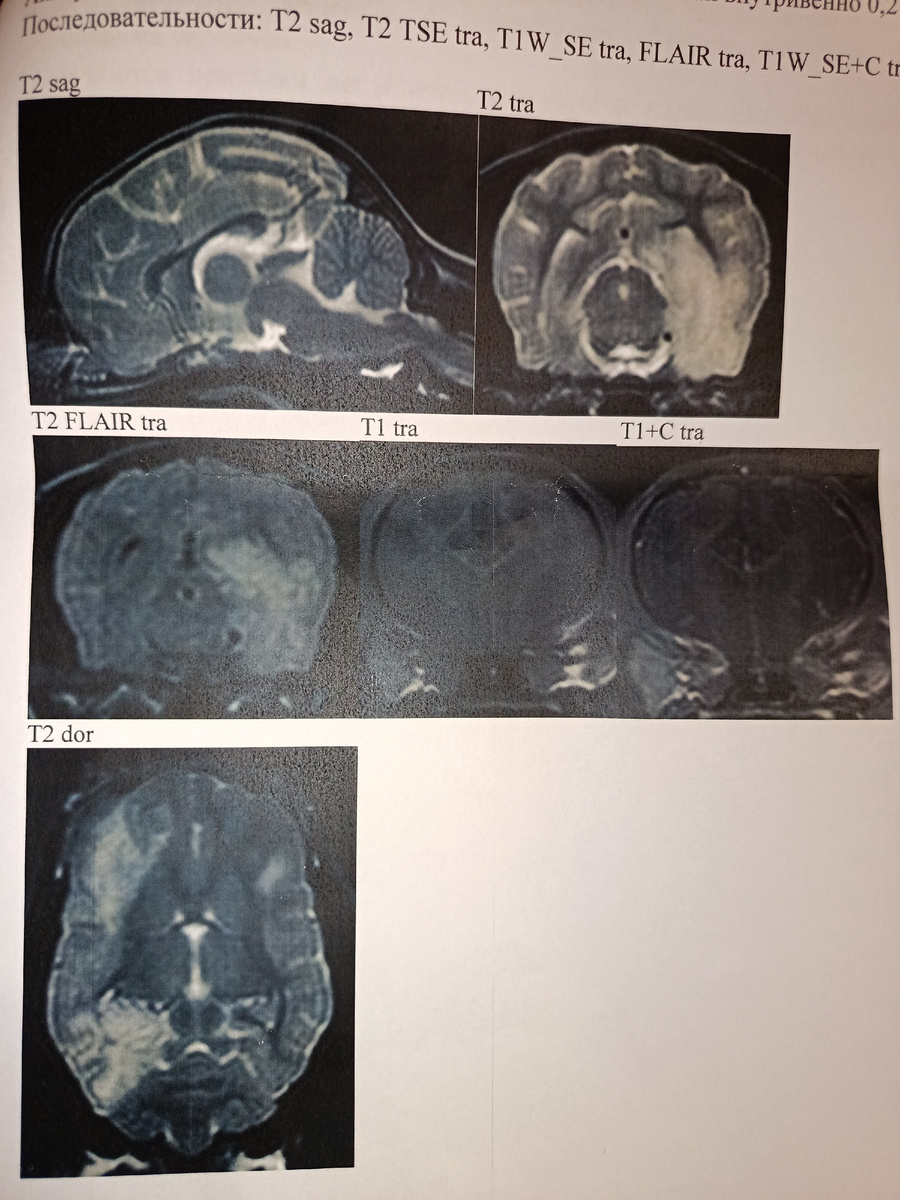

Из протокола МРТ.Белами отмечены зоны поражения. Больше всего пострадало правое полушарие.

Зашли в клинику. Ждали уже там. И наконец-то нас позвали. Вышел сам врач, который проводил МРТ. Простыми словами он сказал, что у Фили не эпилепсия, а менингоэнцефалит йорков, который бывает у данной породы. Сказал, что в последнее время очень много случаев. Порекомендовал записаться к неврологу, чтобы он назначил лечение. Показал на снимке пораженные зоны, и сказал, что скорее всего придется пожизненно лечиться, но это уже обговорить с врачем.